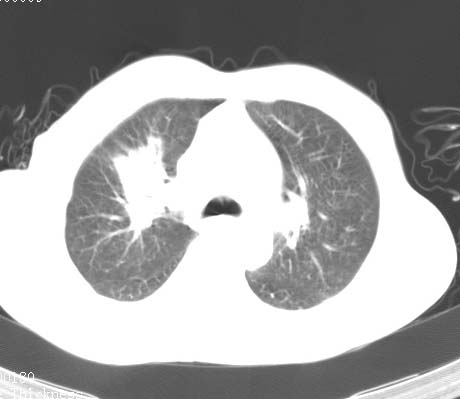

标题: CT14027:男性病人 71岁 咳嗽咳痰数周. [打印本页]

标题: CT14027:男性病人 71岁 咳嗽咳痰数周.

男性病人 71岁 咳嗽咳痰数周.诊断结核应该有保障吧!

支持双上肺继发性肺结核。

tb应无悬念